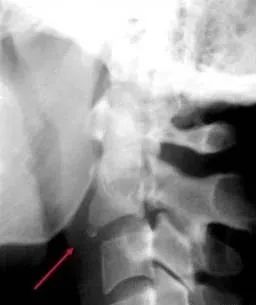

二、寰椎后弓骨折

是C1常见的骨折,常由于过伸位损伤造成,不伴有神经损伤,可伴有先天畸形。